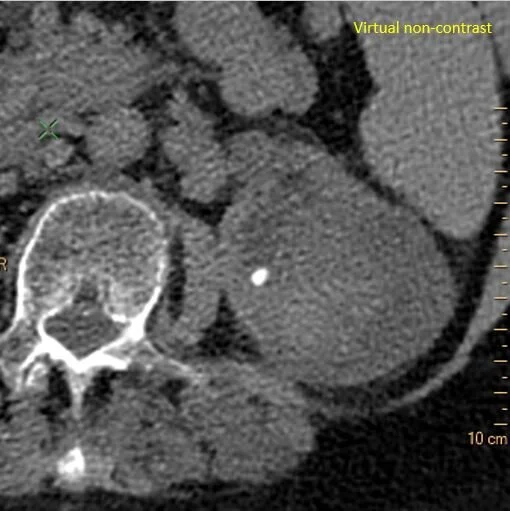

Virtual non-contrast: Solid component remains dense

Virtual non-contrast: Solid component is about 37 HU in density, proving no enhancement.